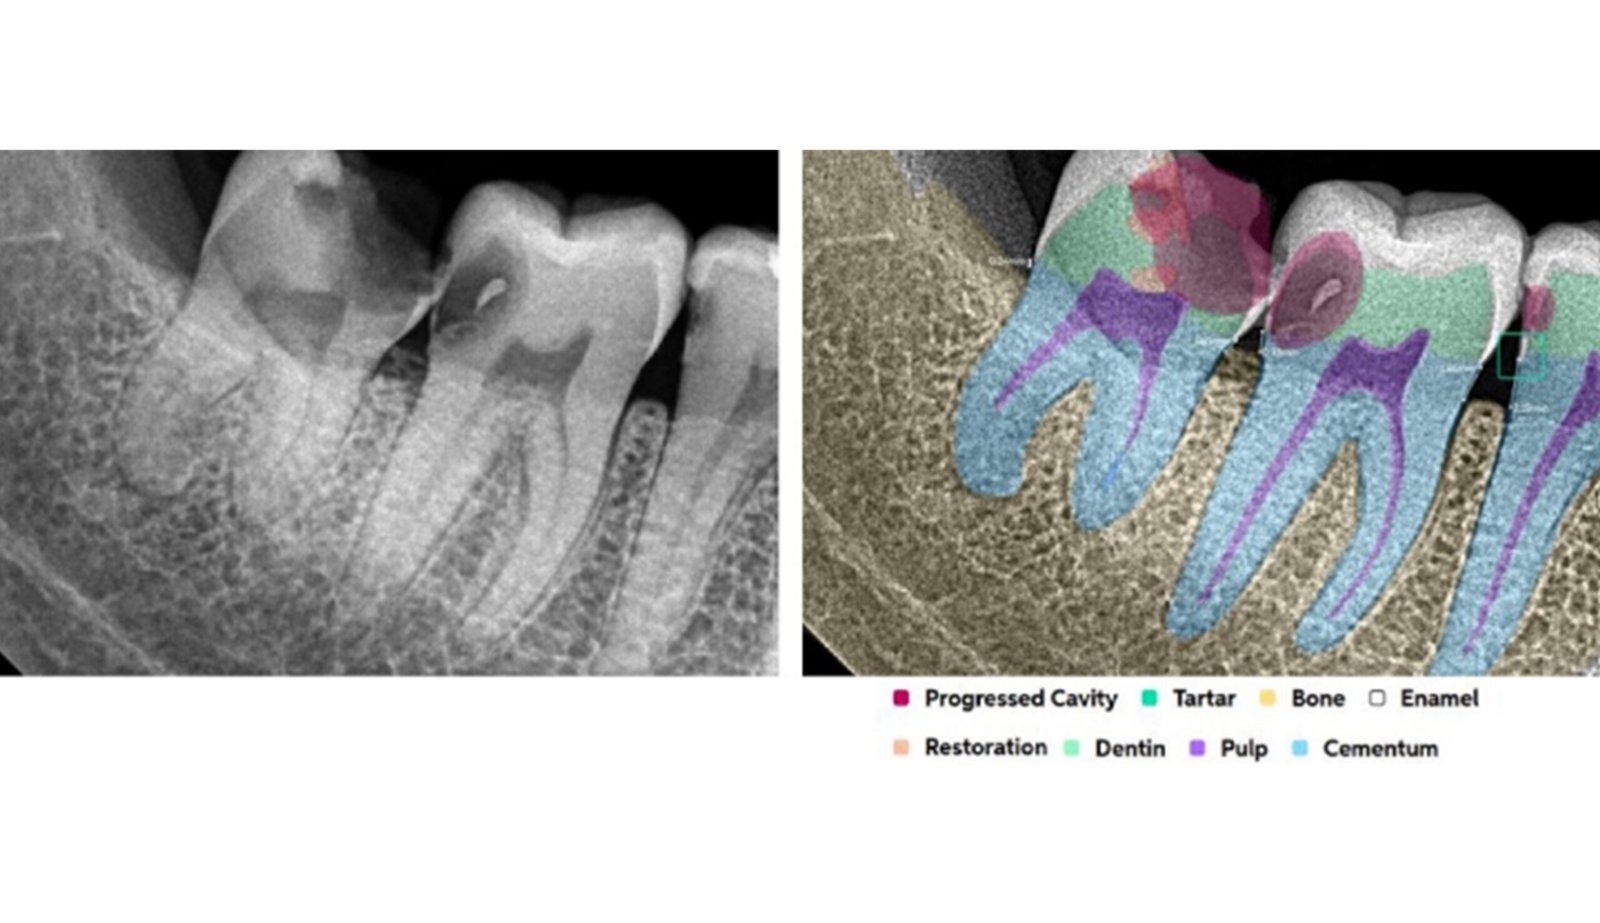

Leveraging AI-driven simulations, this segment integrates predictive modeling with clinical design. We optimize prosthetic, implant, and restorative solutions by forecasting mechanical performance, identifying risk areas, and supporting data-driven treatment planning.